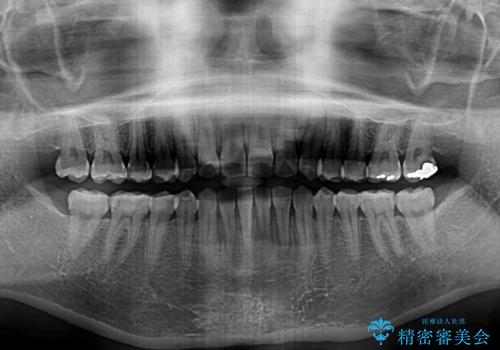

- ワイヤーではない矯正治療があると聞いたとのことで来院された患者様です。

長年前歯のデコボコを気にしていたもののワイヤー矯正に抵抗があり躊躇していたそうですが、インビザラインなら治療してみたいとのことで相談にいらっしゃいました。

インビザライン適用の歯列であったため、歯と歯の間を削るIPRを用いて改善することとしました。

下顎前歯の叢生が顕著な場合、歯列改善後に歯と歯と歯肉の間にブラックトライアングルという隙間ができてしまいます。

軽減することはできますが、完全に解決することは矯正治療のみでは不可能なため、リスクとして事前に周知しておく必要があります。